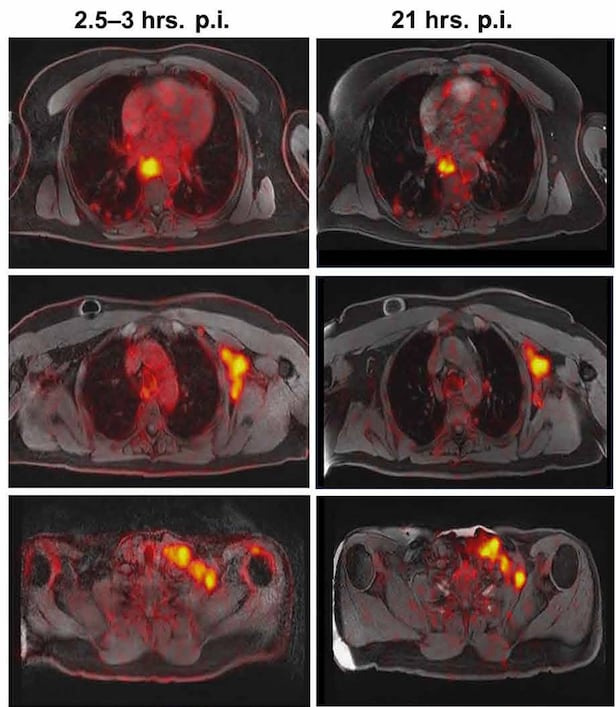

연구진은 실제 위암 환자 7명을 모집해 피브린을 이용한 위암 진단이 가능한지 확인했다. 참가자 7명 중 3명은 항암 치료를 받은 상태였으며, 2명은 말기 환자로 암세포가 다른 장기로 전이까지 된 상태였다. 환자들은 피브린과 결합하는 조영제를 투여 받고 PET를 촬영했다. 그 결과, 기존 환자들이 앞서 진단 받은 암조직 53개가 모두 영상으로 확인됐다.

미국 매사추세츠 종합병원(MGH) 연구진이 개발한 피브린 기반 양전자 단층 촬영(PET) 결과. 붉은 색으로 빛나는 곳이 피브린이 많은 곳이다. 암 조직의 위치와 정확히 일치한다./사이언스 중개의학